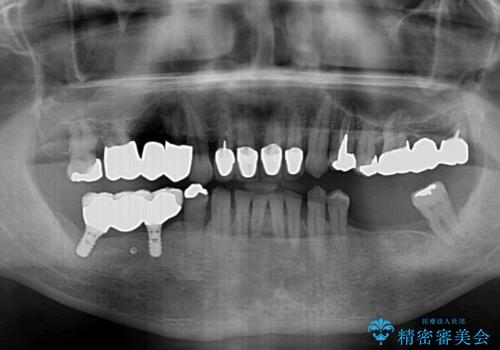

- 奥歯が咬みにくく、前歯がぐらぐらするとのことで来院された患者様です。

咬合力が強く、奥歯が欠損している状態でした。

欠損部はインプラントによる補綴治療を行うこととし、臼歯部が安定した後に、上下前歯部をオールセラミッククラウンにて補綴治療を行うこととしました。